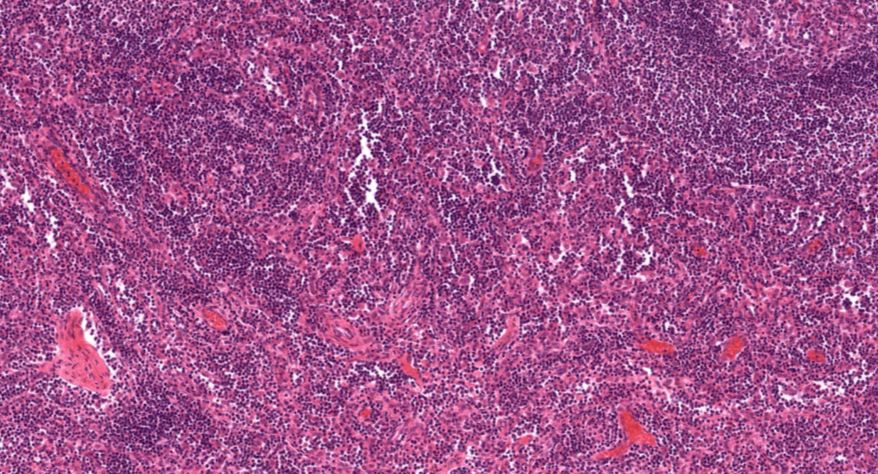

低倍镜:胸腺表面包有薄层结缔组织构成的被膜,结缔组织深入实质,将胸腺分成许多不完整的小叶。每个小叶分为周围的皮质和中央的髓质两部分。皮质中胸腺细胞排列密集,故染色深;髓质中胸腺细胞较少,胸腺上皮细胞多,故染色浅,其中可见染成红色的圆形小体-胸腺小体。高倍镜:胸腺小体大小不等,由几层至十几层扁平的胸腺上皮细胞呈同心圆状排列而成,其外周的细胞较幼稚,细胞核明显;小体中央部分的上皮细胞已退化,细胞核消失,胞质呈均质状,染成红色。

1.成人胸腺全景图